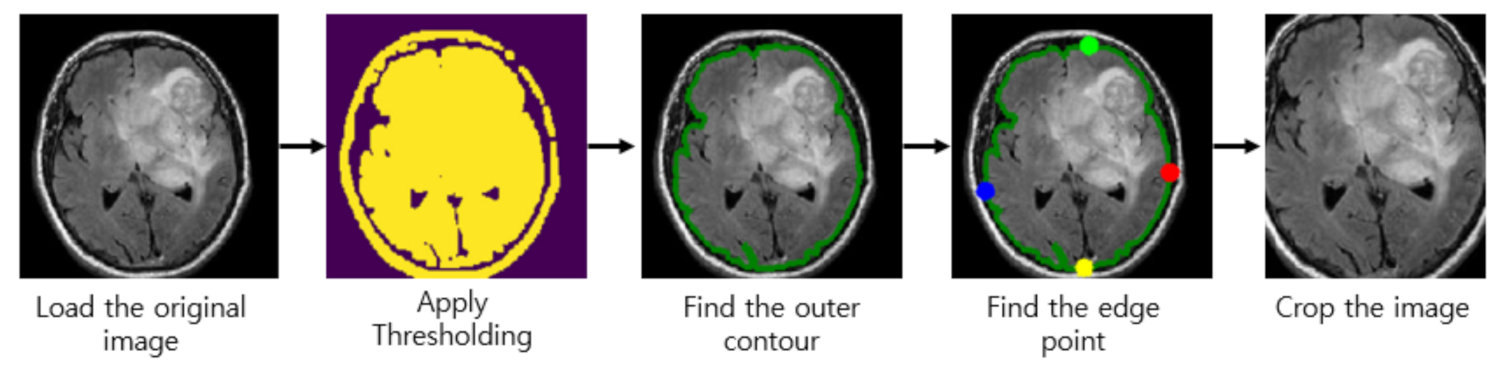

Almost every image in our brain MRI datasets contains undesired spaces and areas, leading to poor classification performance. Hence, it is necessary to crop the images to remove unwanted areas and use only useful information from the image. We use the cropping method in [40] which uses extreme point calculation. The step to crop the MR images using extreme point calculation is shown in Figure 2. First, we load the original MR images for pre-processing. After that, we apply thresholding to the MR images to convert them into binary images. Also, we perform the dilation and erosions operations to remove the noise of images. After that, we selected the largest contour of the threshold images and calculated the four extreme points (extreme top, extreme bottom, extreme right, and extreme left) of the images. Lastly, we crop the image using the information of contour and extreme points. The cropped tumor images are resized by bicubic interpolation. The specific reason to choose the bicubic interpolation is that it can create a smoother curve than other interpolation methods such as bilinear interpolation and is a better choice for MR images since there is a large amount of noise along the edges.

Figure 2.

Step to crop the magnetic resonance (MR) images.